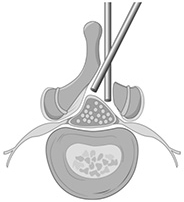

MED法の応用として腰部脊柱管狭窄症でも除圧できます(MEL法)

反対側の除圧をしています

内視鏡手術(MEL法)で術後脊柱管を拡大したところ